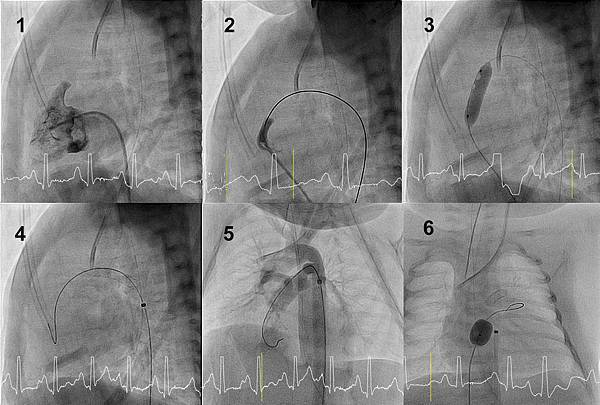

肺動脈瓣閉鎖 無心室中隔缺損 (Pulmonary atresia with intact ventricular septum, PA-IVS)是一種嚴重的發紺性心臟病,不治療,幾乎不可能長期存活。過去,在新生兒時期接受開心手術是唯一的治療方式。王主科教授在20多年前開始發展以心導管技術打通閉鎖肺動脈瓣這項可以取代開刀的治療。經過多年的經驗累積與治療策略調整,如今以心導管貫穿肺動脈瓣膜儼然成為大多數條件適合的病童的治療首選,而台大兒童心臟團隊更是全世界這項心導管治療個案數與治療成績最頂尖的團隊之一。